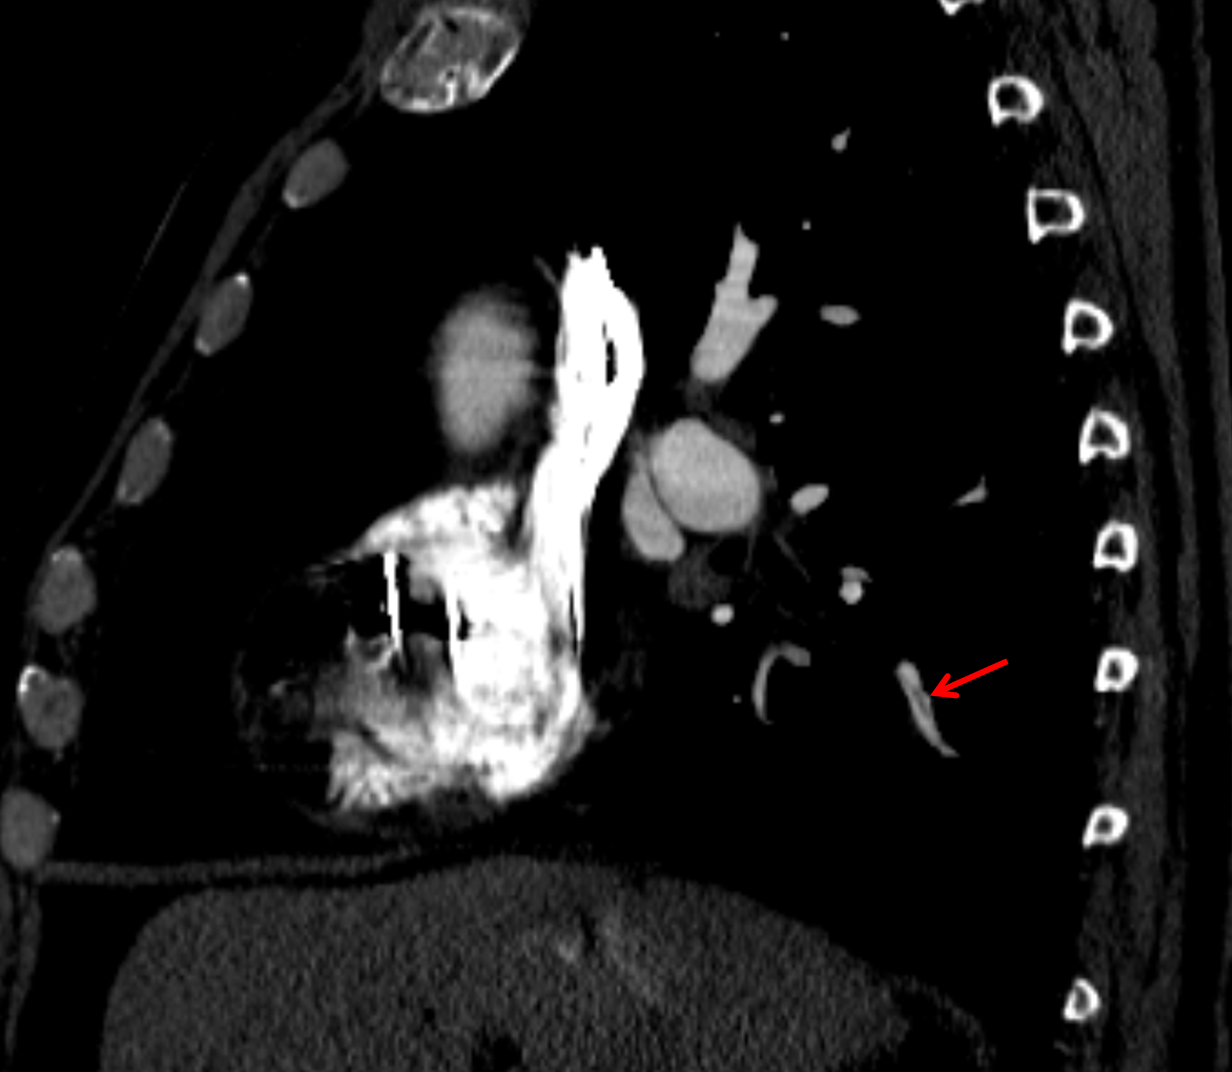

Left ventricular pseudoaneurysm arising from the basal inferior wall with peripheral thrombus and mural calcification. Recommend correlation with any available prior imaging to document stability. Further imaging followup can be dictated by outpatient cardiology referral.